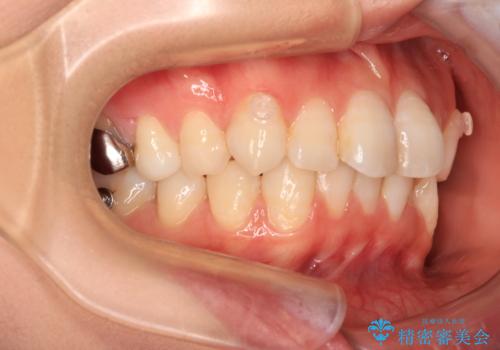

- 上下前歯のデコボコを改善したいとのことで来院された患者様です。

マウスピースを長時間装着し続ける自信はあまりないとのことでしたが、目立たない装置であれば頑張って装着するとのことで、インビザラインによる矯正治療を行うこととしました。

初めの1年くらいは何とか頑張って装着してくださいましたが、途中から変化をあまり感じられなくなり、日々の装着時間は徐々に短くなってしまいました。

前歯のデコボコはもっと改善できましたが、3年半が経過し、初診時と比べたら大幅に良くなったとのことで終了することとなりました。